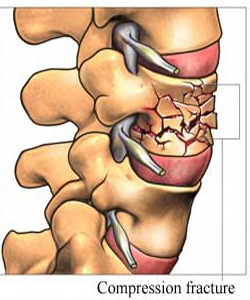

Η οστεοπόρωση είναι μια σιωπηρή νόσος, δεν παρουσιάζει συμπτώματα για μεγάλο χρονικό διάστημα. Αυτό σημαίνει ότι περνάνε αρκετά χρόνια, κατά τη διάρκεια των οποίων η οστεοπόρωση συνεχώς χειροτερεύει από πλευράς απώλειας οστικής μάζας και διαταραχής της μικροαρχιτεκτονικής δομής των οστών, μέχρι να εμφανιστεί το πρώτο της σύμπτωμα, που είναι το κάταγμα. Η οστεοπόρωση είναι νόσος όλων των οστών και γι’ αυτό κατάγματα μπορεί να συμβούν σε διάφορες θέσεις του σκελετού, αλλά συνήθως συμβαίνουν στους σπονδύλους, στον αυχένα του μηριαίου οστού και στο αντιβράχιο. Πιο συγκεκριμένα, περίπου 40% των οστεοπορωτικών καταγμάτων αφορούν τη σπονδυλική στήλη, 20% τον αυχένα του μηριαίου οστού, 20% το αντιβράχιο και 20% διάφορα άλλα οστά. Τα κατάγματα του αυχένα του μηριαίου οστού και του αντιβραχίου συμβαίνουν πάντοτε μετά από έναν χαμηλής βίας τραυματισμό, όπως είναι η πτώση από την όρθια θέση, ενώ συνοδεύονται πάντοτε από πόνο. Αντίθετα, τα σπονδυλικά κατάγματα συμβαίνουν συχνά χωρίς να προηγηθεί τραυματισμός και αρκετές φορές δεν συνοδεύονται από πόνο στη ράχη ή στη μέση παρά μονάχα από ένα ελαφρύ αίσθημα καύσου. Απώλεια ύψους και κύφωση αποτελούν όψιμες εκδηλώσεις της οστεοπόρωσης και οφείλονται σε σπονδυλικά κατάγματα.